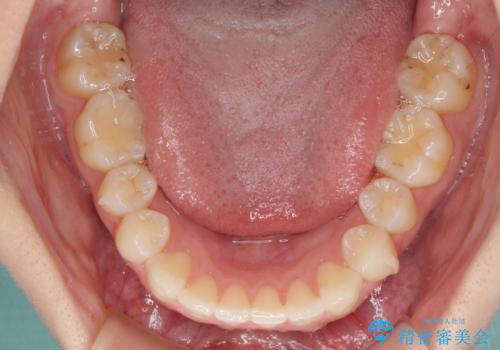

- 前歯のデコボコと上下のクロスバイトを気にして来院された患者様です。

インビザラインを用い、IPR(歯と歯の間を削る)と歯列全体を拡大させることで、歯並びを整えていくこととしました。

上の前歯が下の前歯を乗り越える際、奥歯がほとんど咬めない時期があり、乗り越えた後も、インビザライン特有の奥歯の咬みにくさが続きました。

咬み合わせ改善のために治療期間を要しましたが、最終的に奥歯はしっかりと咬めるようになりました。